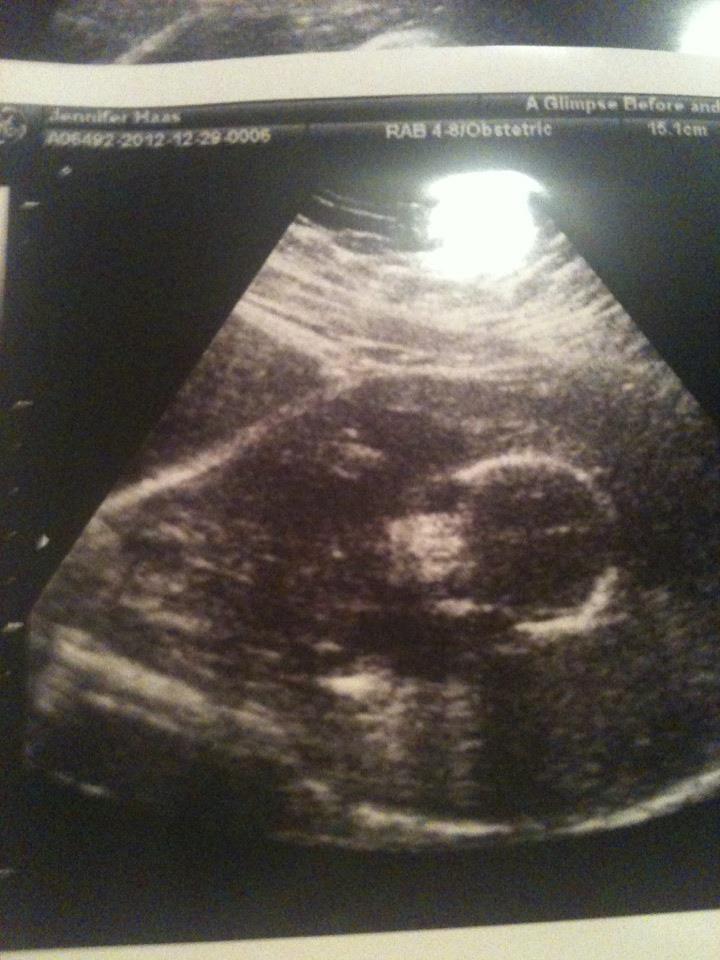

| Baby Haas' photo debut. Heartbeat a strong 176 -10 weeks. |

| Gender reveal at 18 weeks- it's a girl! |

| Her little legs were up by her face. Very proud of showing off the goods :).18 weeks |